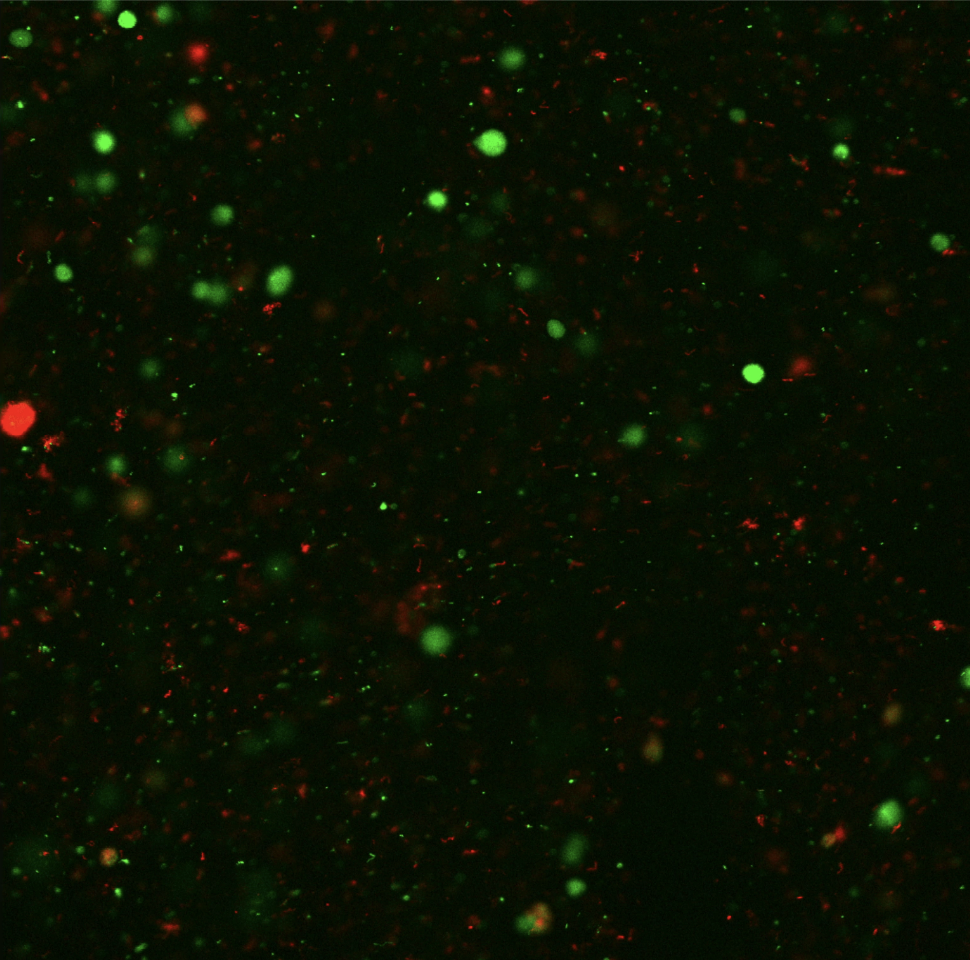

Implanting cells into hydrogel and performing live/dead stain assay.

Bioreactor grown canine organoids.